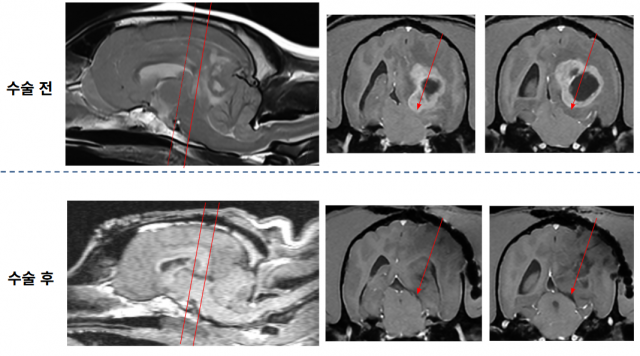

이번 환자는 12살 웰시코기 암컷으로, 갑작스러운 기립 불능과 의식 저하를 보여 내원했다. 초기 신경학적 검사에서는 전반적인 신경 반응 저하와 연하반사 부재가 확인돼 중증의 뇌신경계 이상이 의심됐다. MRI 검사 결과, 좌측 대뇌반구 심부에 종괴성 병변이 발견됐으며, 광범위한 뇌부종, 대뇌낫의 우측 변위, 소뇌 압박 및 초기 탈출 소견, 뇌간 압박까지 동반해 매우 위중한 상태였다.

뇌종양은 뇌 심부에 위치해 기존 수의학적 접근법이 없었기 때문에 이안동물신경센터에서는 인의 신경외과에서 활용하는 후방 경피질 접근법(Posterior Transcortical Approach)을 최초로 적용했다. 뇌-현미경을 이용한 이 접근법은 측두-두정엽 후방 피질을 통과해 심부 구조로 접근하는 고난이도 수술로, 뇌간 근처 종양도 안전하게 제거할 수 있으며, 수술 중 제3뇌실의 정상적인 뇌척수액 흐름 회복도 확인됐다. 수술 직후 MRI에서는 뇌간 압박이 완전히 해소됐고, 자발 호흡이 회복돼 약 6시간 후 발관이 가능해졌다.

수술 후 1일 차에는 좌측 위협 반사 외 모든 신경학적 기능이 정상화돼 스스로 기립하고 보행할 수 있었으며, 수술 후 2일 차의 뇌파검사에서는 정상 범주의 뇌파 패턴이 재출현했다. 6일 차에는 폐렴도 호전돼 퇴원했으며, 현재는 일상생활에 지장이 없을 정도로 정상적인 신경학적 기능을 유지하고 있다. 수술 후 영상에서 종양이 제거된 것이 확인되며, 종양에 의해 발생했던 뇌간 압박이 해소된 모습이 보인다.